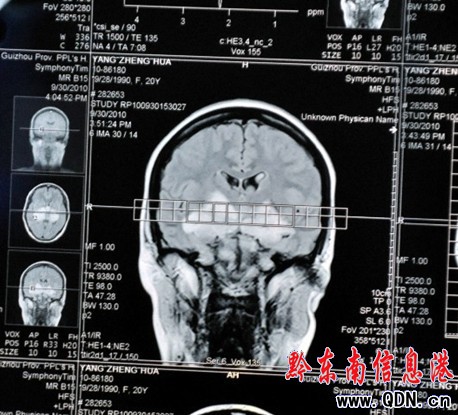

醫生診斷說,在楊正花的大腦里,有不明物體存在。記者通過這張照片看到,這個不明物體形狀很像一只正在煽動著翅膀的“蝴蝶”(如圖)。黔東南州家庭教育學會講師、中醫師潘思緯在看了診斷照片后認為,楊正花大腦中的“蝴蝶”極有可能就是腫瘤,它壓迫了視覺神經,導致失明。